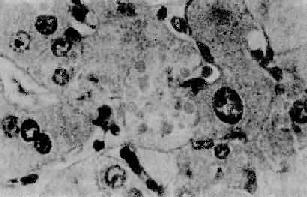

2.酒精性肝炎(alcoholic hepatitis)在有临床肝症状表现的病例,常出现3种病变:肝细胞脂肪变性,酒精透明小体(alcoholic hyalin,AH 图10-42)形成和灶状肝细胞坏死伴中性粒细胞浸润。

图10-42 酒精性肝炎

图中央区肝细胞浆内见成群的酒精透明小体